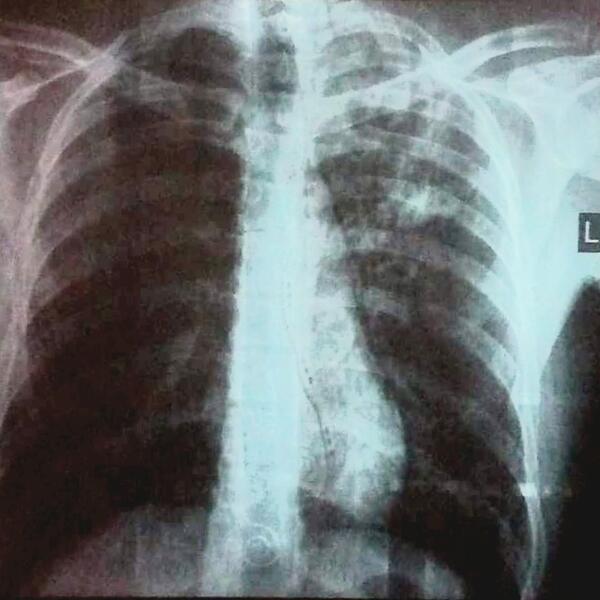

- Najčešći simptomi tuberkuloze su: malaksalost, gubitak apetita i mršavljenje, pojačano noćno znojenje, povišena temperatura, uz kašalj koji je najčešće suv i uporan, a ređe praćen iskašljavanjem sluzi, gnoja ili krvi. Otežano disanje može biti prisutno ako je bolest uznapredovala, a bolovi u grudima se javljaju ukoliko je zahvaćena plućna maramica. Ako su zahvaćeni drugi organi, bolest se manifestuje tegobama vezanim za njih. Preporuka je da se kod svih osoba koje kašlju duže od tri nedelje uradi rendgenski snimak pluća da bi se isključila tuberkuloza ili neka druga plućna bolest, kaže doktorica Plavšić.

Dijagnozu tuberkuloze postavlja isključivo pulmolog na osnovu anamnestičkih podataka, pregleda i obavezne radiografije grudnog koša koja je neophodna i najvažnija dijagnostička metoda.

Snimci pluća pacijenta obolelog od tuberkuloze: